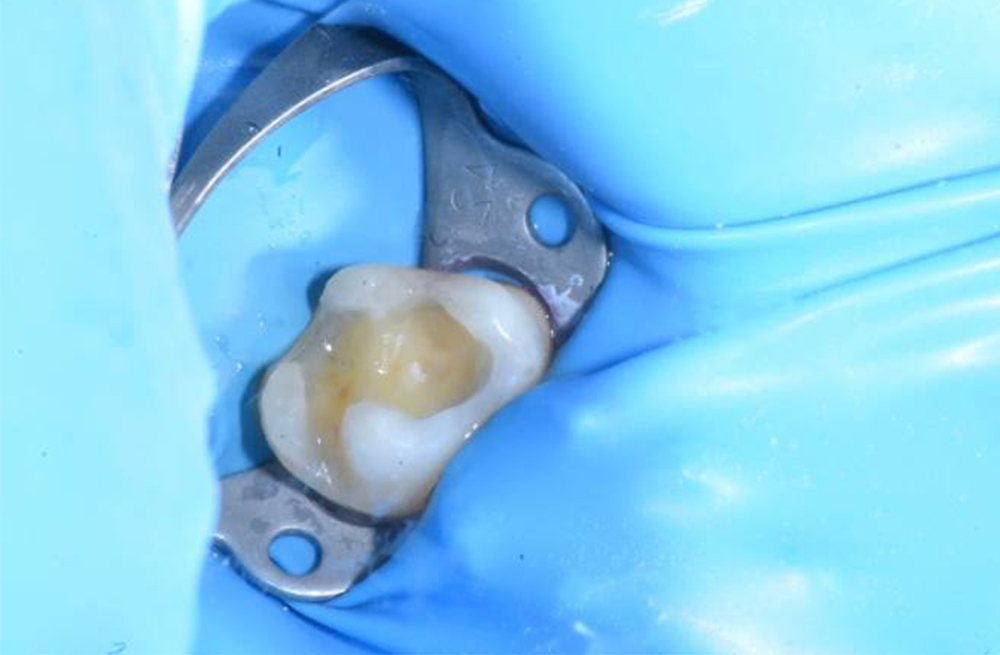

Лечение глубокого кариеса жевательных зубов под микроскопом с сохранением нерва и восстановлением контактного пункта

Точная диагностика и качественная реставрация при глубоком кариозном поражении моляра и премоляра

Замена негерметичной пломбы после диагностики скрытого кариеса в жевательном зубе

Удаление негерметичной пломбы и лечение вторичного кариеса зуба с поражением глубоких слоёв дентина